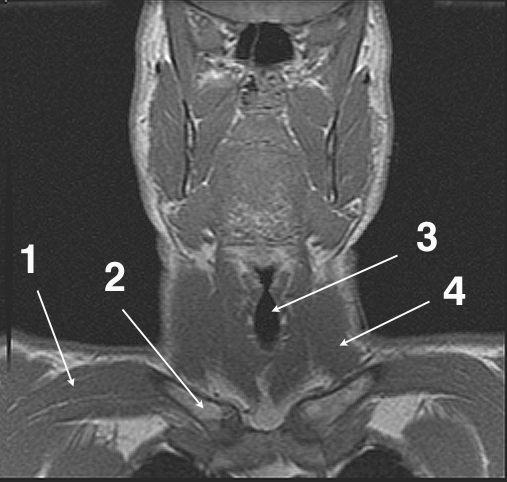

Identifications